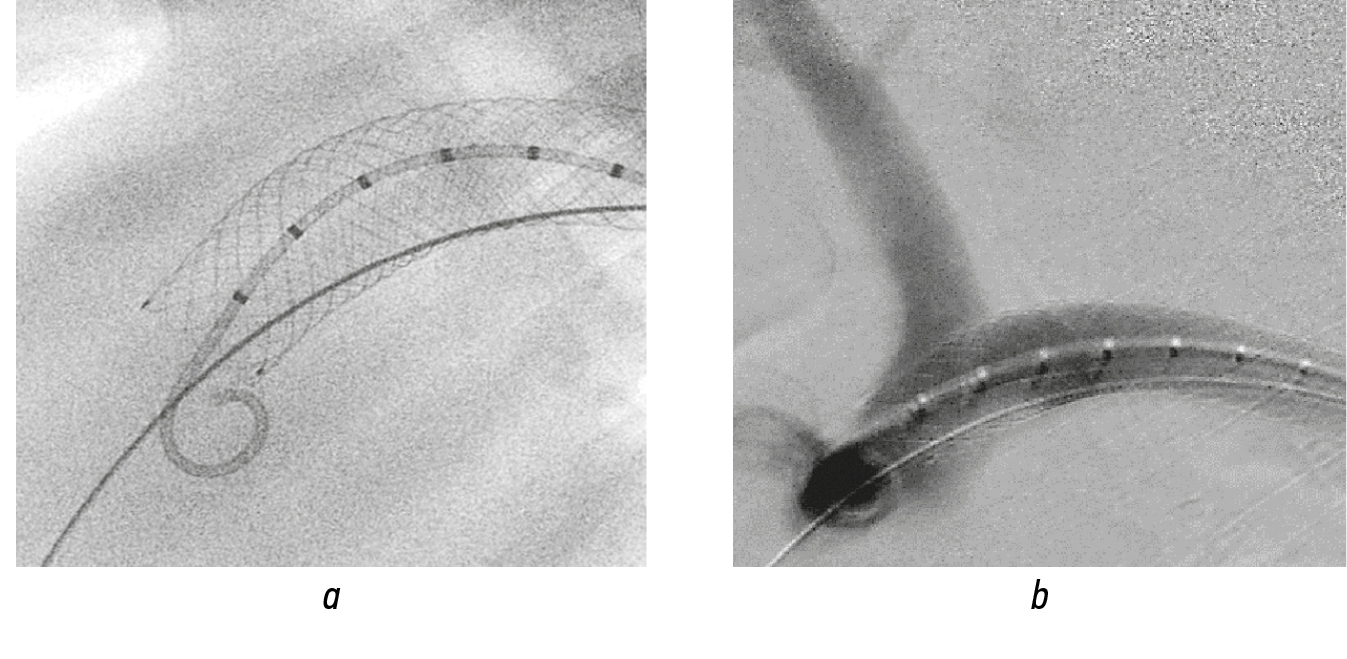

Endoprosthetics of the aortic arch. Under angiographic control, through a transfemoral approach, the main trunk of the structure was retrogradely inserted into the aortic arch. For positioning, the implantation level was proximal to the brachiocephalic trunk (Fig. 12, a). The control image clearly visualized the brachiocephalic trunk. This demonstrates sufficient permeability of the graft wall for blood and contrast agent (Fig. 12, b). Then, by focusing on the created RoadMap mask, in the area of the orifice of the brachiocephalic trunk, a guidewire with a guide catheter was used to fenestrate the outer membrane, the guidewire was inserted into the arterial lumen, and the guide catheter was removed (Fig. 13, a). Then, the fenestrated part was dilated with a balloon catheter (Fig. 13, b). The outlet module of the stent graft on a balloon with the appropriate diameter was inserted into the prepared hole along the guidewire, and the balloon was inflated. In this case, the proximal end of the module was securely fixed in the cell of the main trunk (Fig. 13, c). The balloon was removed along with the guide. During the acquisition of the control image, the structure was passable, and the orifice of the brachiocephalic trunk was clearly visualized. No endoleak was noted (Fig. 13, d).

Fig. 12. Aortic arch replacement: а — stent graft implanted into the aortic arch; b — control angiogram of the brachiocephalic trunk

Fig. 13. Stages of branching of a stent graft implanted in the aortic arch: а — personalized fenestration of the graft wall; b — balloon dilatation of fenestration; c — discharge module at the mouth of the brachiocephalic trunk; d — control angiogram